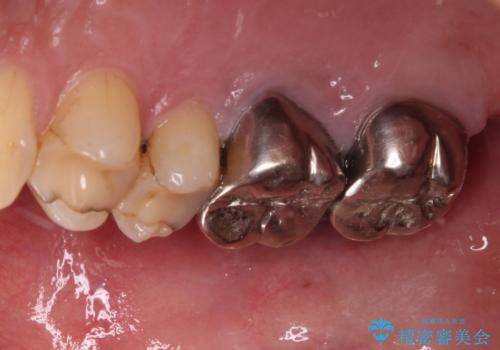

- 目立つ銀歯と欠けて痛みを感じる歯を気にして来院された患者様です。

目立つ銀歯も根管治療を行い、その後2本の歯をオールセラミッククラウンにて補綴治療を行うこととしました。

大臼歯では、根管治療後にも痛みが残ってしまったため、外科的歯内療法(歯根端切除術)を適用しました。外科処置直後は腫れや痛みなどがありましたが、半年が経過し、痛みがなくなり、レントゲン写真上でも炎症の消退が認められました。